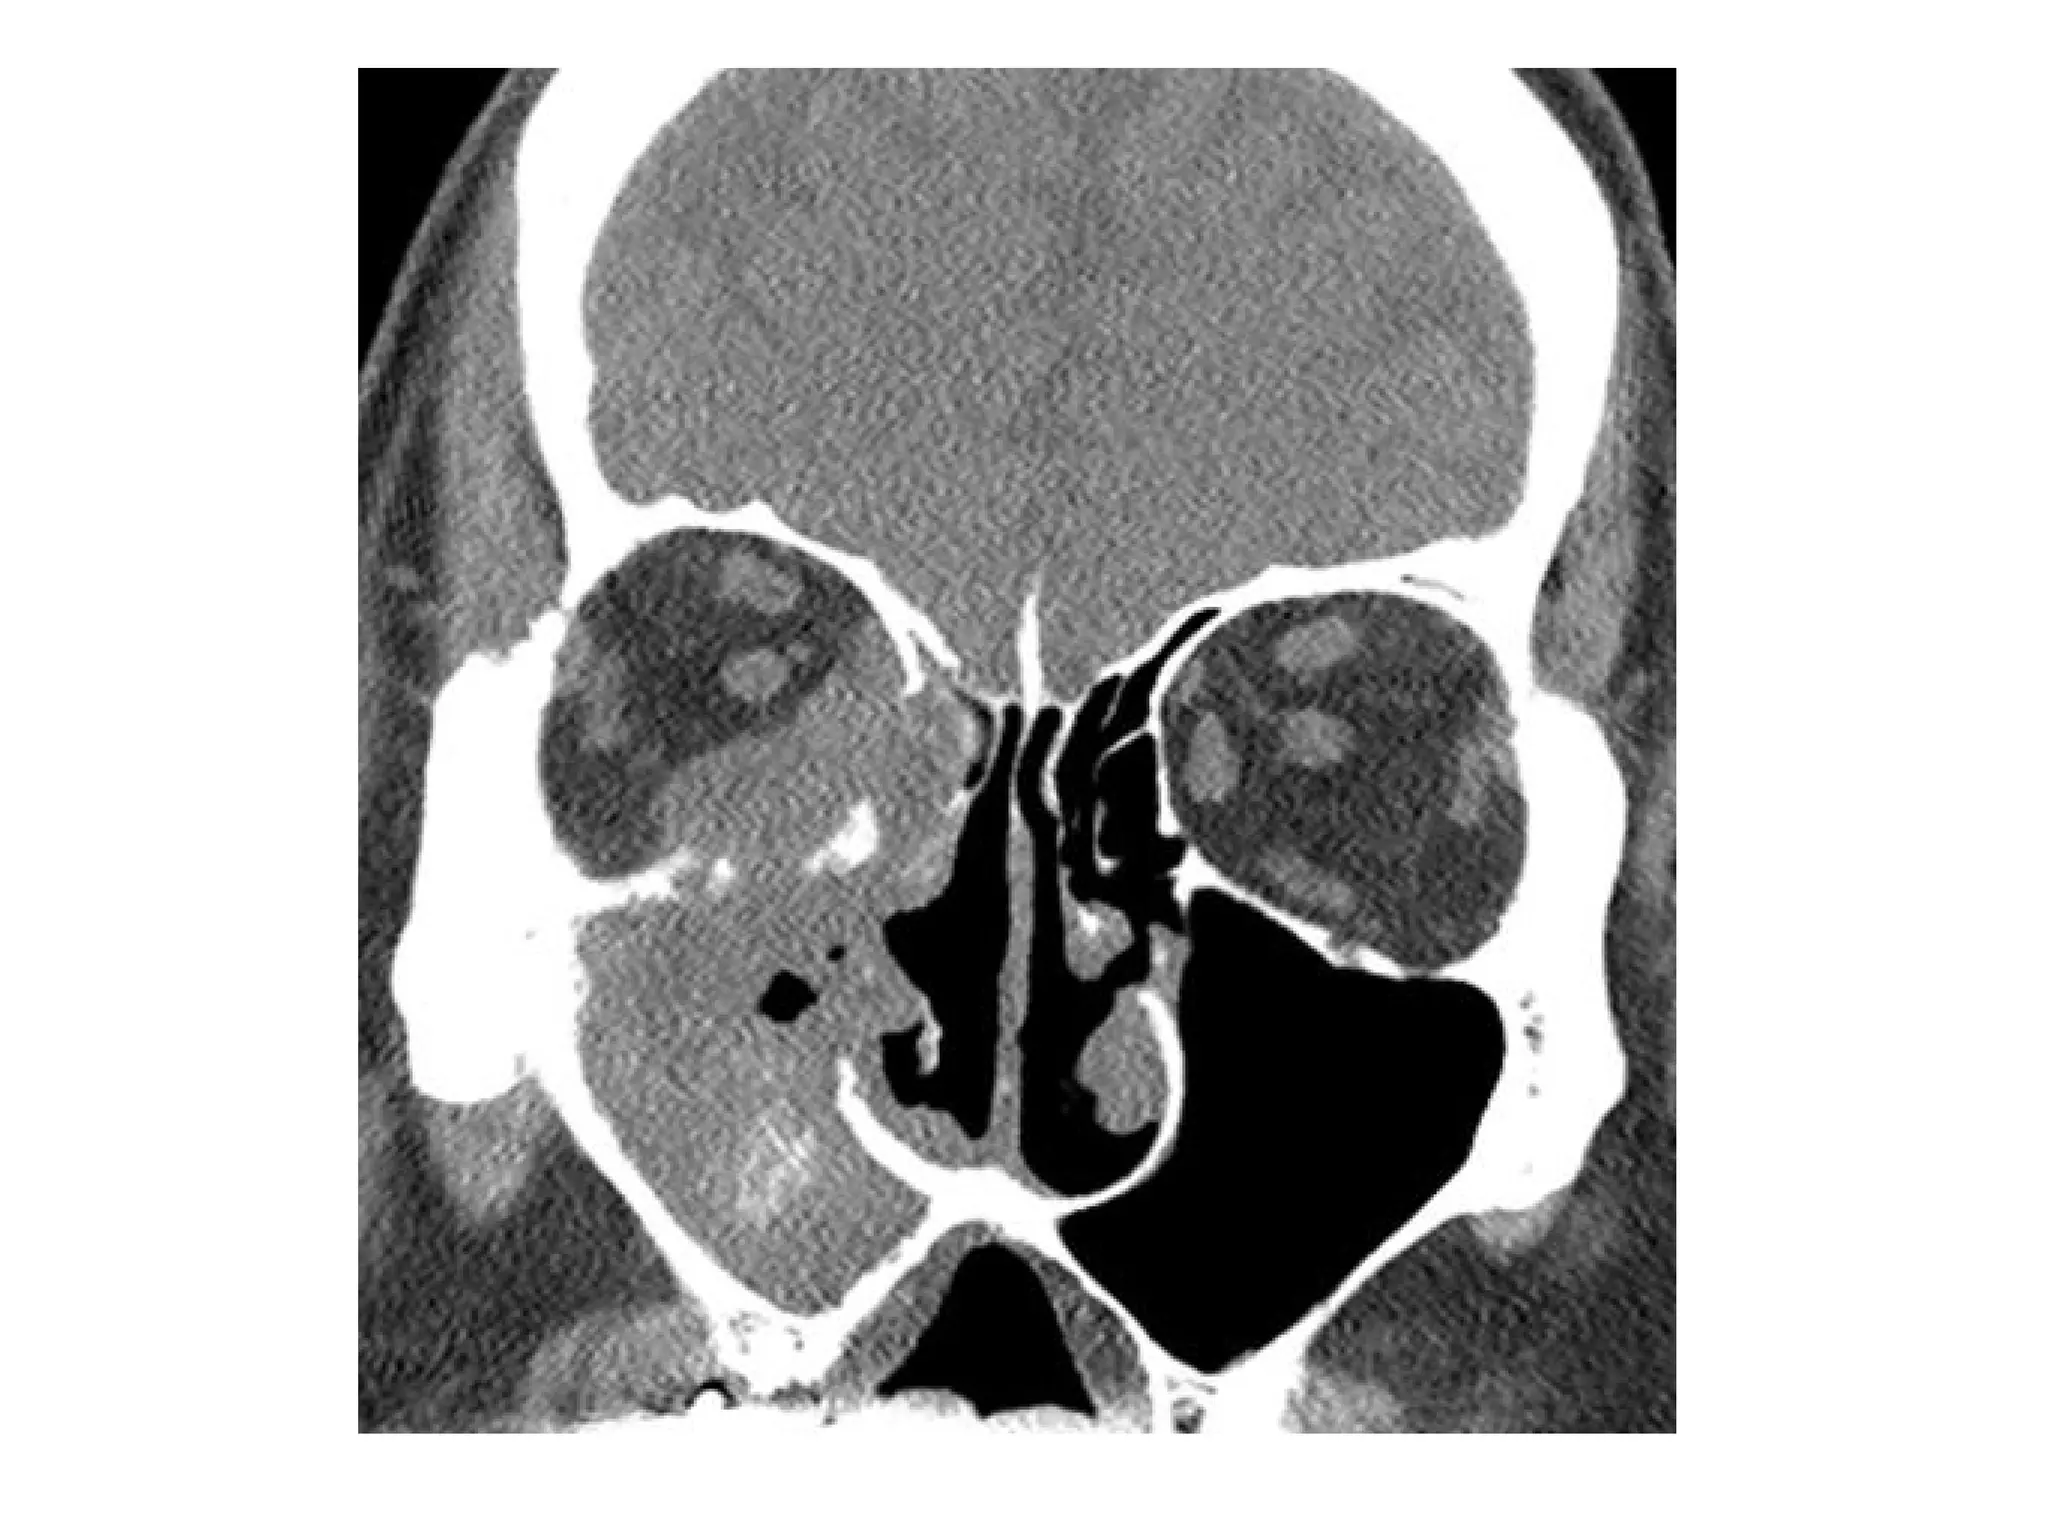

Sinusitis with orbital subperiosteal abscess

Subperiosteal abscess, (a) axial CT+C in a soft tissue window showing

opacified ethmoid sinuses; preseptal cellulitis (*); and a small crescent

shaped soft tissue mass (arrow) adjacent to the lamina papyracea, (b)

Coronal CT+C in another patient with opacification of the right ethmoid sinus

(E) and a crescent shaped fluid collection adjacent to the medio-superior

orbital wall